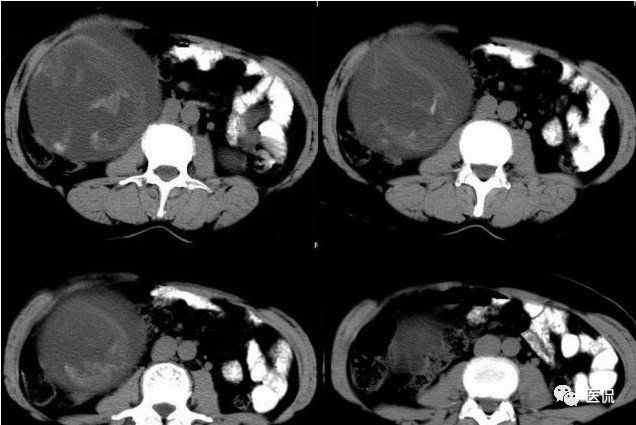

腹腔内残留的纱布在人体内引起渗出或液化坏死并纤维包裹形成异物性脓肿(纱布瘤)。纱布瘤的影像特点:圆形或卵圆形肿块,较大,有完整包膜,薄壁,较少的情况下为厚壁,边界较完整,增强后薄膜可以持续强化。不同时期的纱布瘤可以有不同表现:早期(10个月或半年内)多表现为蜂窝状;2~5年内一般表现为囊性飘带状;10~20年之后则为实性软组织密度,包膜钙化呈钙化网状结构。手术过程中残留在人体内的医用纱布所形成的肿瘤样病变。

手术所见:腹腔内无腹水,肿块位于右上腹,约15x10x8cm大小 ,周围网膜包裹粘连,向胆囊三角处延续,呈囊性,与周围结构无明显浸润,仔细分离粘连,逐步游离暴露肿块,见肿块与右肾及结肠、十二指肠无明显关系,初步确定为肿大的胆囊,继续向肝门部游离,见肿块与胃窦粘连,因分离困难,决定切开肿块。穿刺肿块有黄色脓液抽出,考虑胆囊脓肿,切开囊壁,吸出大量黄色混浊脓液约1200ml,探查囊腔,见粘膜层为胆囊粘膜,腔内有一异物残留,经证实为医用盐水纱布,取出纱布约15x15cm大小,封存。继续游离胆囊至完整切除,检查囊壁无明显占位病变。

腹腔内遗留纱布团的影像学表现,以B超较具特征性,其主要表现为:腹腔或盆腔内特殊率减的黑色包块,后方伴有扇形衰减的声影,上窄下宽,好似一“黑色大布”,早期包块内含有不规则光团或光点,随时间延长有缩小或消失,为纱布团内气体。CT的优势在于早期常表现为软组织密度的肿块,其内可见多少不等的气泡,随时间的延长气泡逐渐被吸收减少至消失,增强扫描可见包膜不同程度强化而内容物无强化。熟悉其影像学表现,可在术前作出明确诊断。